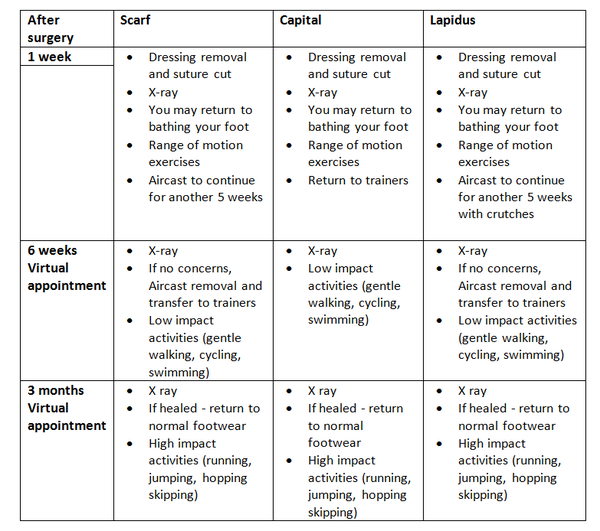

Discharge

Before you leave the hospital, you will be given an Aircast Walker following the Scarf and Lapidus procedures or a post-operative sandal in the case of a capital osteotomy. You will be shown how to partially weight bear on the foot using crutches. Post-operative painkillers will be dispensed by the nurses along with your next appointment.

You must rest with the leg elevated for the first 48 hours (essential walking only). It is important that you do not interfere with the dressings and keep them dry. You can buy a purpose made waterproof cover to keep the leg dry, from your chemist (Limbo M100 above the knee).

Full recovery takes between seven to twelve months.